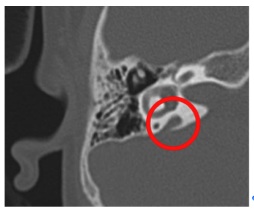

Abbiamo reclutato 39 bambini affetti da UHL che si sono presentati presso la struttura complessa di audiologia e otorinolaringoiatria dell'IRCCS �Burlo Garofolo� nel periodo compreso tra gennaio 2012 e agosto 2013. Per valutare l'eziologia tutti sono stati valutati da un team multidisciplinare, 34 sono stati sottoposti a tomografia computerizzata ad alta definizione dell'osso temporale (HDTC, Figura 3) e/o a risonanza magnetica e a 17 � stato somministrato un questionario da noi elaborato, per valutare l'impatto della patologia sulla vita socio-relazionale. Come gruppi di controllo sono stati reclutati un gruppo di pazienti normoacusici e un gruppo di pazienti con ipoacusia bilaterale (BHL).

Figura 3. Tomografia computerizzata ad alta definizione dell'osso temporale (HDTC).